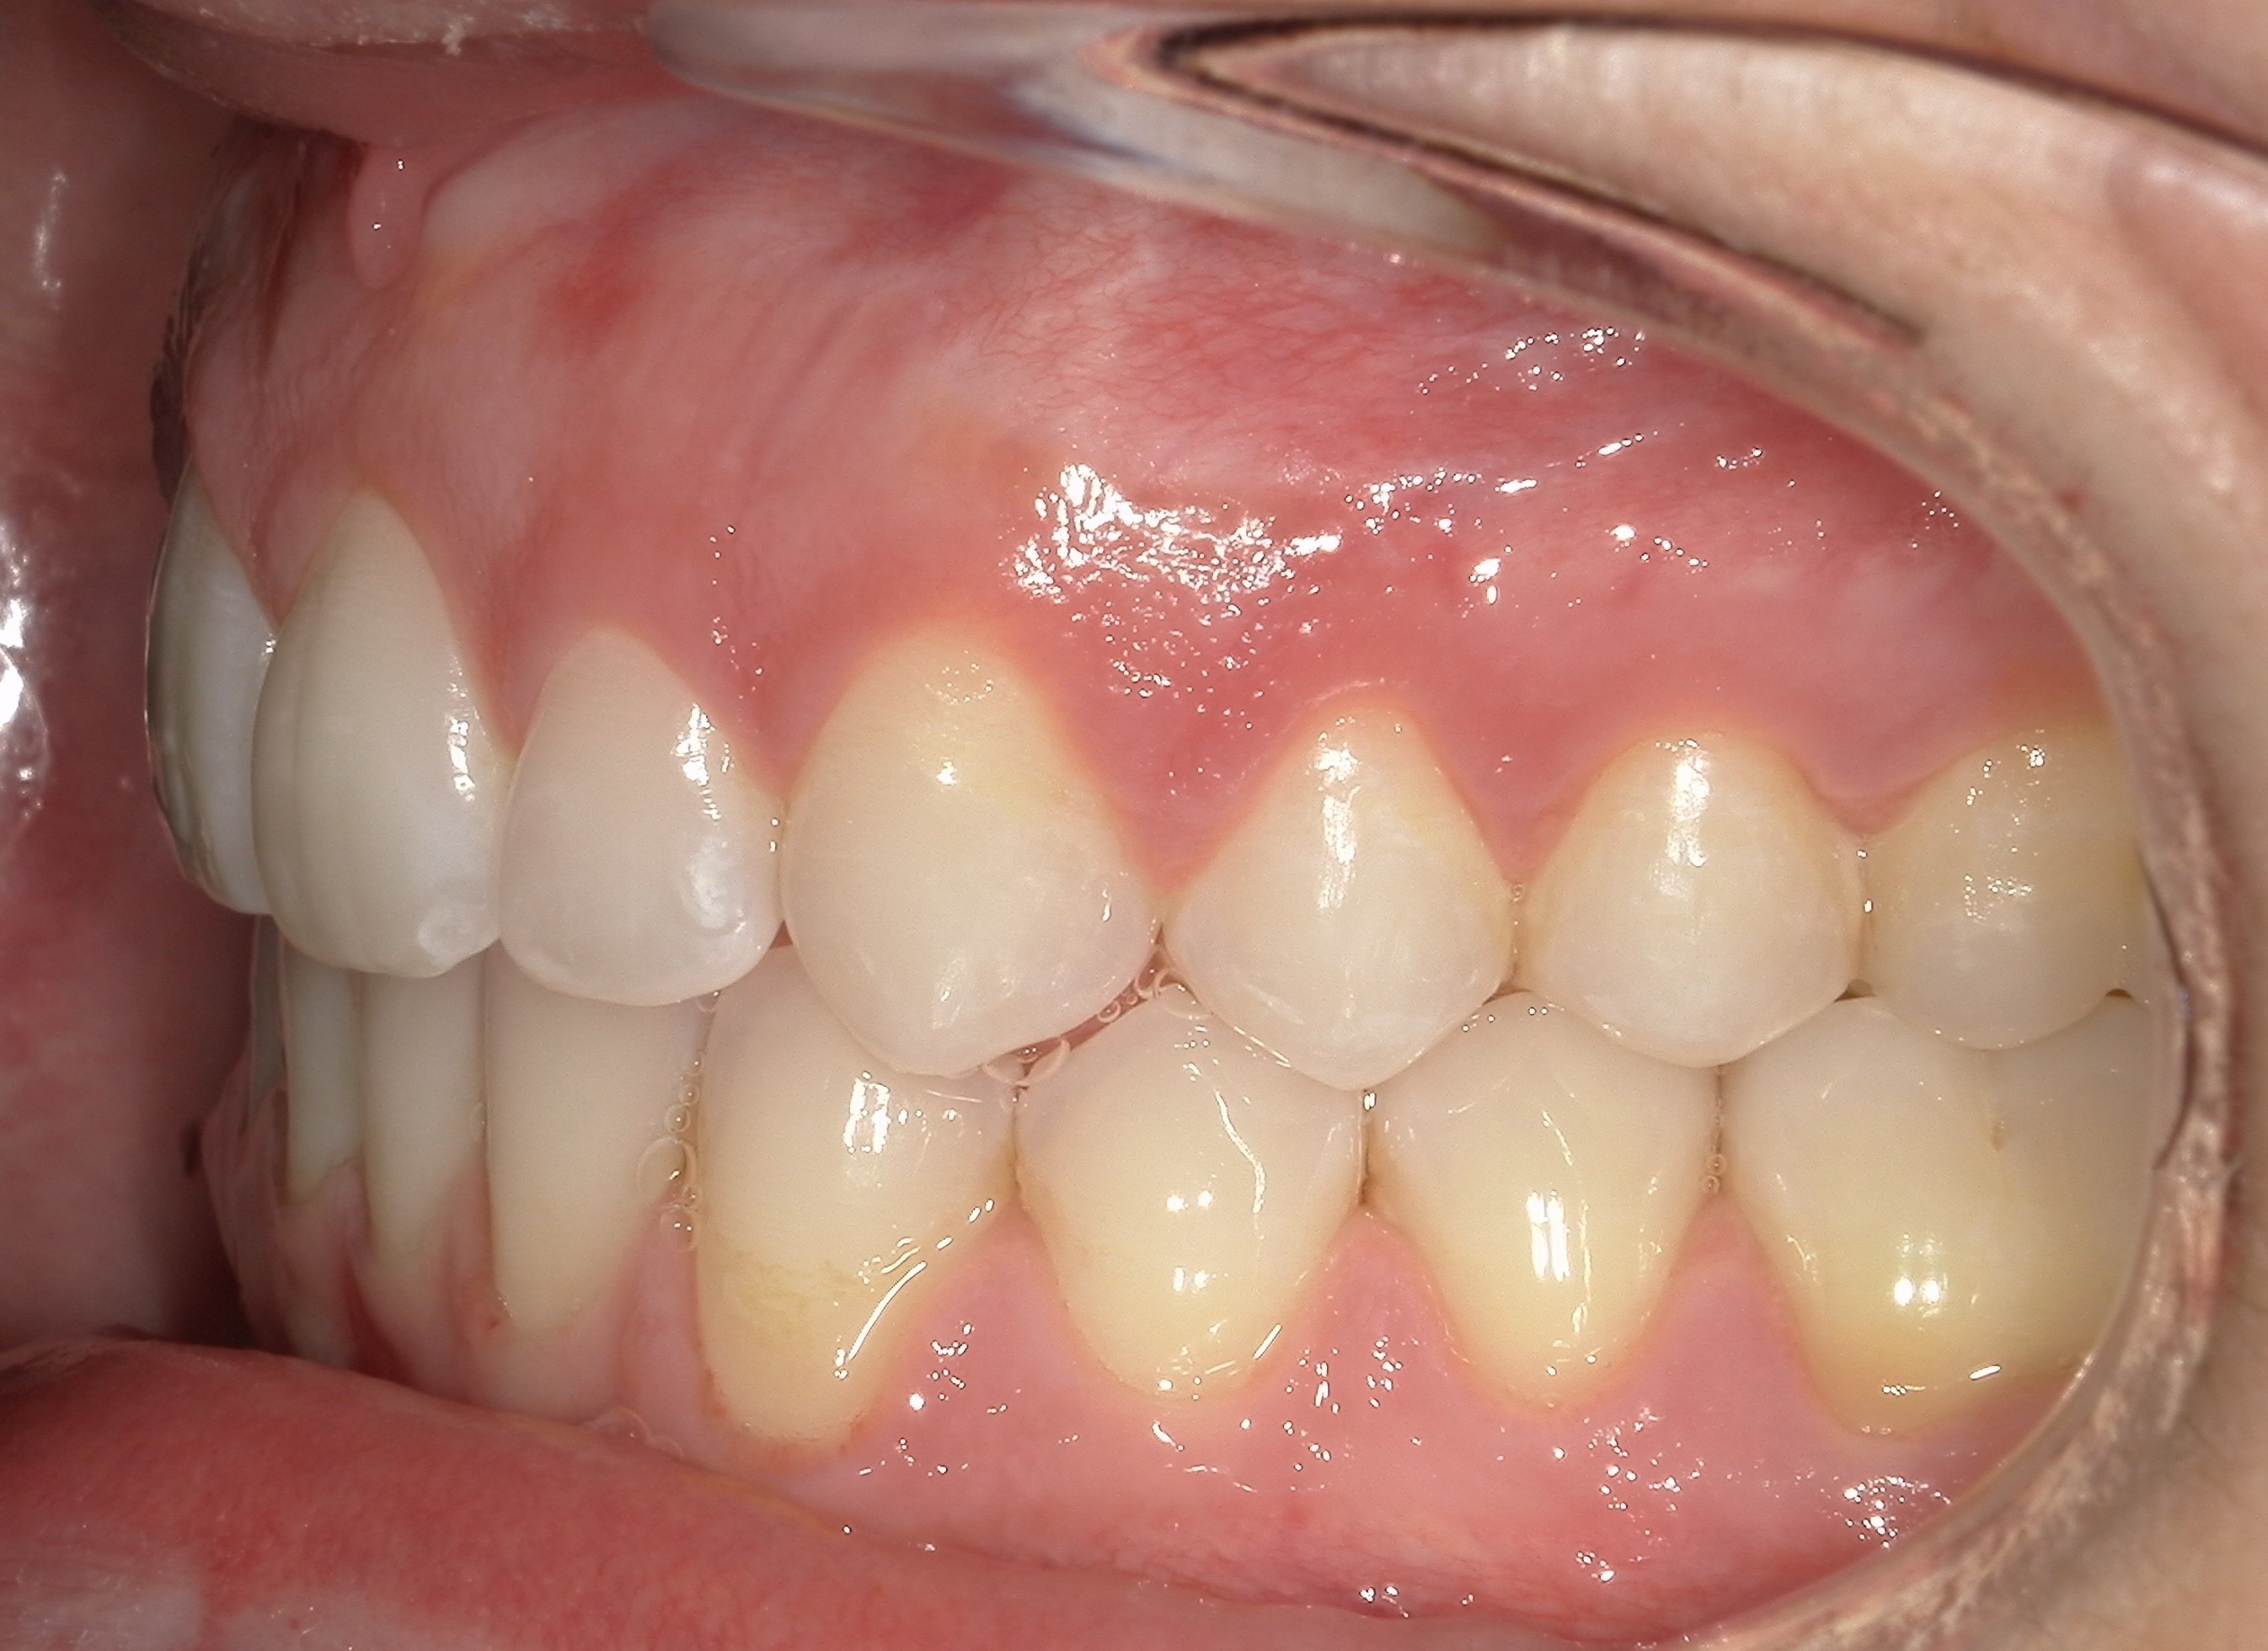

Initial treatment

INTRAORAL

Diganosis: Moderate lower anterior crowding, square and narrow maxilla, rotated #19

Adjuncts: Attachments